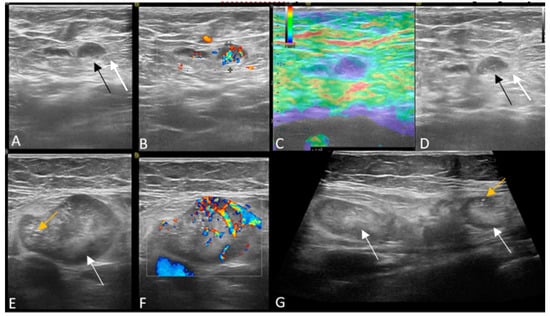

Figure 3. (AD) Patient with negative genetic testing and positive axillary US. There is a lymph node with focal cortical thickening (white arrow), increased vascularity and stiff strain elastography appearance. (EG) Patient with CHEK2 mutation and positive axillary US. There are multiple, irregular lymph nodes, with eccentric hilum (white arrow), thickened cortex with punctate microcalcs (yellow arrow) and chaotic, periphery vascularity.